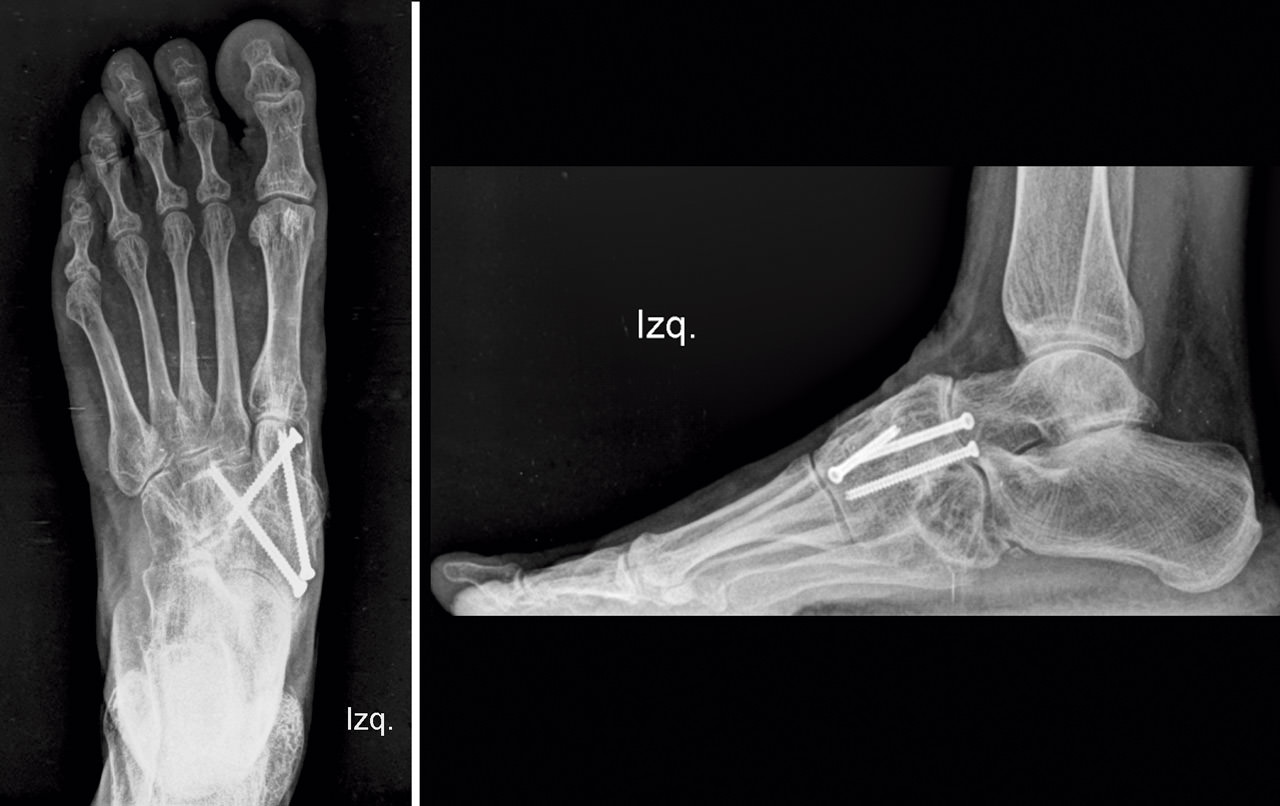

En el postoperatorio, la paciente llevó una inmovilización con férula de yeso las 2 primeras semanas y una bota de yeso durante 4 semanas más. A partir de las 6 semanas se le autorizó la carga con una ortesis de tipo Rom Walker®. A los 3 meses se comprobó la consolidación con el estudio radiológico (Figura 6), retirándose la ortesis, y se inició el tratamiento rehabilitador. Tras un periodo de 8 semanas de tratamiento fisioterápico, la paciente se recuperó satisfactoriamente y volvió a realizar sus actividades normales sin molestias.

Figura 6. Estudio radiológico a los 3 meses.